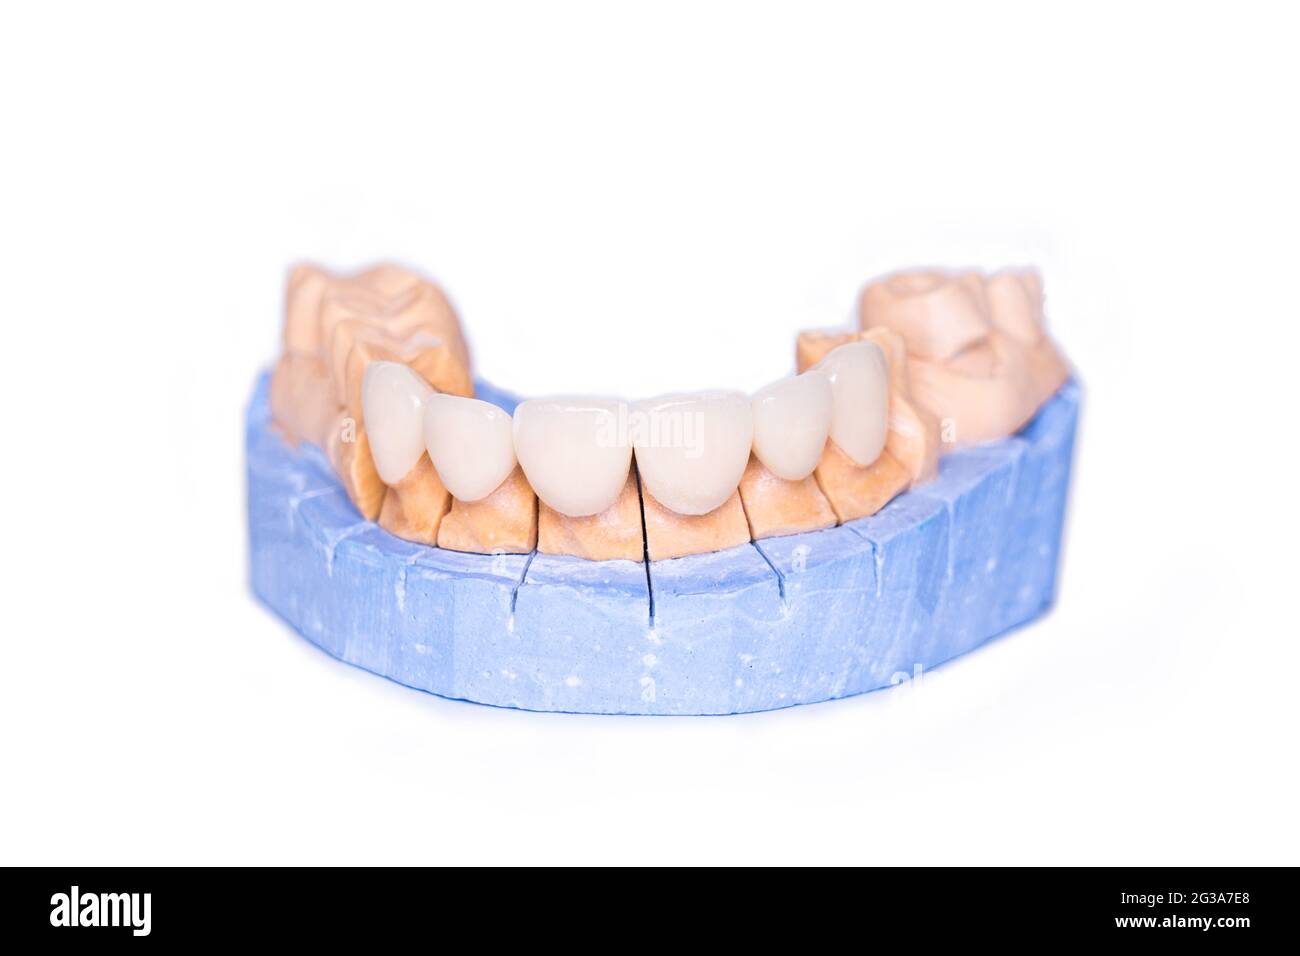

Boiseries et couronnes isolées sur fond blanc. Modèle de plâtre de dents. Modèle de plâtre à mâchoire inférieure avec dents préparées. Plâtre démontable de travail Banque D'Imageshttps://www.alamyimages.fr/image-license-details/?v=1https://www.alamyimages.fr/boiseries-et-couronnes-isolees-sur-fond-blanc-modele-de-platre-de-dents-modele-de-platre-a-machoire-inferieure-avec-dents-preparees-platre-demontable-de-travail-image446363296.html

Boiseries et couronnes isolées sur fond blanc. Modèle de plâtre de dents. Modèle de plâtre à mâchoire inférieure avec dents préparées. Plâtre démontable de travail Banque D'Imageshttps://www.alamyimages.fr/image-license-details/?v=1https://www.alamyimages.fr/boiseries-et-couronnes-isolees-sur-fond-blanc-modele-de-platre-de-dents-modele-de-platre-a-machoire-inferieure-avec-dents-preparees-platre-demontable-de-travail-image446363296.htmlRF2GX5GX8–Boiseries et couronnes isolées sur fond blanc. Modèle de plâtre de dents. Modèle de plâtre à mâchoire inférieure avec dents préparées. Plâtre démontable de travail

Boiseries et couronnes isolées sur fond blanc. Modèle de plâtre de dents. Modèle de plâtre à mâchoire inférieure avec dents préparées. Plâtre démontable de travail Banque D'Imageshttps://www.alamyimages.fr/image-license-details/?v=1https://www.alamyimages.fr/boiseries-et-couronnes-isolees-sur-fond-blanc-modele-de-platre-de-dents-modele-de-platre-a-machoire-inferieure-avec-dents-preparees-platre-demontable-de-travail-image432328576.html

Boiseries et couronnes isolées sur fond blanc. Modèle de plâtre de dents. Modèle de plâtre à mâchoire inférieure avec dents préparées. Plâtre démontable de travail Banque D'Imageshttps://www.alamyimages.fr/image-license-details/?v=1https://www.alamyimages.fr/boiseries-et-couronnes-isolees-sur-fond-blanc-modele-de-platre-de-dents-modele-de-platre-a-machoire-inferieure-avec-dents-preparees-platre-demontable-de-travail-image432328576.htmlRF2G3A7E8–Boiseries et couronnes isolées sur fond blanc. Modèle de plâtre de dents. Modèle de plâtre à mâchoire inférieure avec dents préparées. Plâtre démontable de travail

Boiseries et couronnes isolées sur fond blanc. Modèle de plâtre de dents. Modèle de plâtre à mâchoire inférieure avec dents préparées. Plâtre démontable de travail Banque D'Imageshttps://www.alamyimages.fr/image-license-details/?v=1https://www.alamyimages.fr/boiseries-et-couronnes-isolees-sur-fond-blanc-modele-de-platre-de-dents-modele-de-platre-a-machoire-inferieure-avec-dents-preparees-platre-demontable-de-travail-image435058759.html

Boiseries et couronnes isolées sur fond blanc. Modèle de plâtre de dents. Modèle de plâtre à mâchoire inférieure avec dents préparées. Plâtre démontable de travail Banque D'Imageshttps://www.alamyimages.fr/image-license-details/?v=1https://www.alamyimages.fr/boiseries-et-couronnes-isolees-sur-fond-blanc-modele-de-platre-de-dents-modele-de-platre-a-machoire-inferieure-avec-dents-preparees-platre-demontable-de-travail-image435058759.htmlRF2G7PHTR–Boiseries et couronnes isolées sur fond blanc. Modèle de plâtre de dents. Modèle de plâtre à mâchoire inférieure avec dents préparées. Plâtre démontable de travail

Boiseries et couronnes isolées sur fond blanc. Modèle de plâtre de dents. Modèle de plâtre à mâchoire inférieure avec dents préparées. Fonctionnement du mode de plâtre démontable Banque D'Imageshttps://www.alamyimages.fr/image-license-details/?v=1https://www.alamyimages.fr/boiseries-et-couronnes-isolees-sur-fond-blanc-modele-de-platre-de-dents-modele-de-platre-a-machoire-inferieure-avec-dents-preparees-fonctionnement-du-mode-de-platre-demontable-image438019125.html

Boiseries et couronnes isolées sur fond blanc. Modèle de plâtre de dents. Modèle de plâtre à mâchoire inférieure avec dents préparées. Fonctionnement du mode de plâtre démontable Banque D'Imageshttps://www.alamyimages.fr/image-license-details/?v=1https://www.alamyimages.fr/boiseries-et-couronnes-isolees-sur-fond-blanc-modele-de-platre-de-dents-modele-de-platre-a-machoire-inferieure-avec-dents-preparees-fonctionnement-du-mode-de-platre-demontable-image438019125.htmlRF2GCHDT5–Boiseries et couronnes isolées sur fond blanc. Modèle de plâtre de dents. Modèle de plâtre à mâchoire inférieure avec dents préparées. Fonctionnement du mode de plâtre démontable